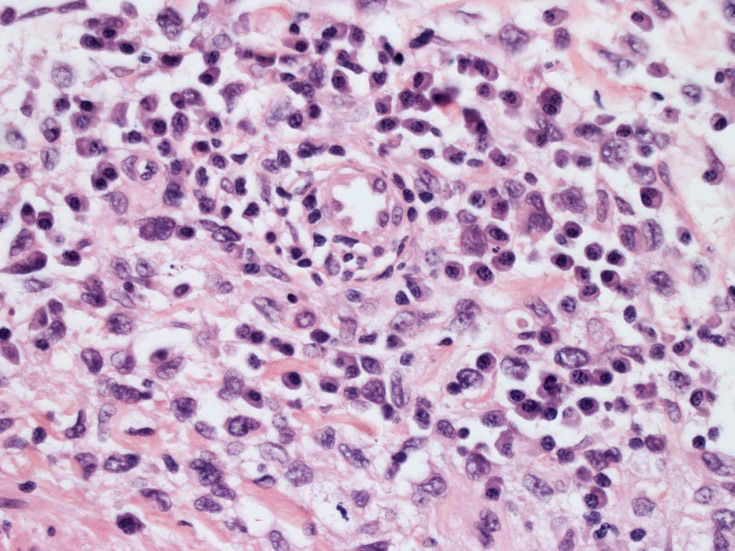

皮膚生検組織。細胞浸潤が表皮, 表皮真皮境界部, 真皮, 皮下組織にびまん性に認められる。血管中心性に結節様の分布があるように見える。

皮膚に異型細胞の浸潤がみられる。異型細胞は表皮内に浸潤するほか、表皮真皮境界部, 真皮, 皮下脂肪組織にもびまん, 結節様の浸潤所見を示す。血管周囲に浸潤、集蔟する所見も多く見られる。 増殖浸潤細胞の核には類円形や腎臓形, またはへこみ, 切れ込み, 溝などを有する多型な核が認められる。クロマチンは粗でvesicularな核が多い。核小体の明らかな核もある。好エオジン性の核内封入体様構造も少数に見られた。mitosisは容易に認められる。hyperchromaticな多型核, bizzarreな細胞が高頻度に認められ異型度は高いと考えられる。細胞質は境界不明瞭, 淡明または泡沫様の 好エオジン性胞体である。